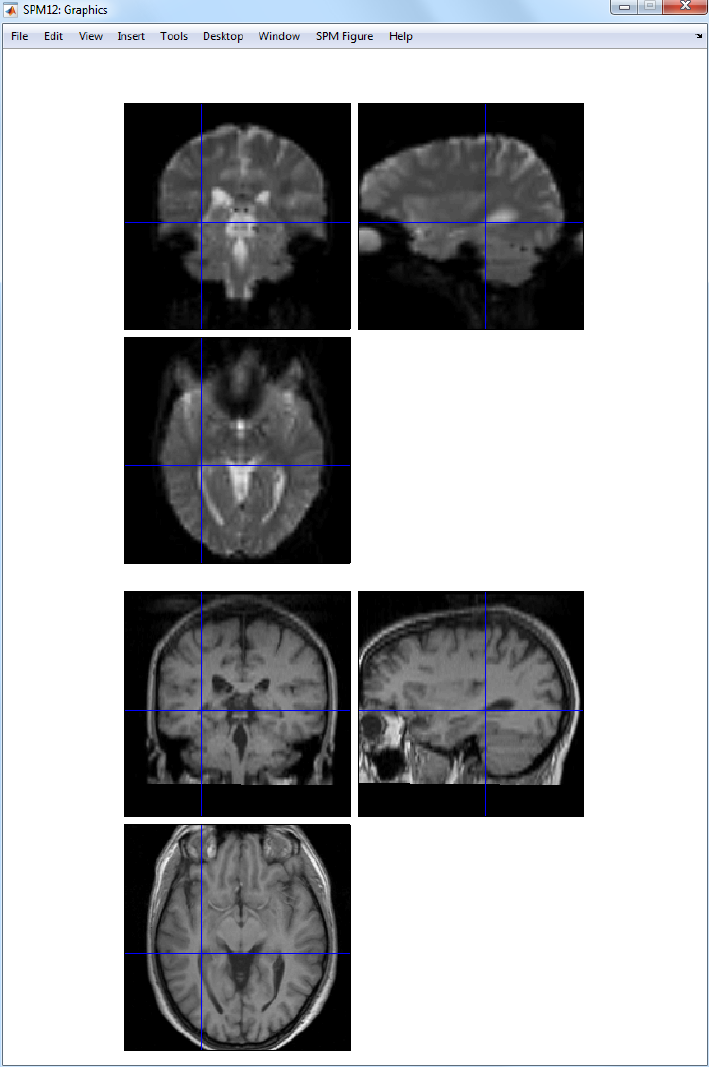

30.2.2 Coregistration ..................................223

31.1.4 Coregistration ..................................248

42.7.3 Coregistration of mean EPI (fMRI) to T1 (sMRI) ..............422